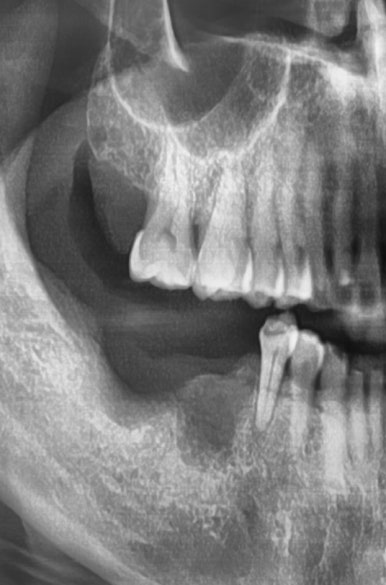

원장님이 해외에서 공부중일 때 다른 치과에서 임플란트를 여러개 하셨는데요

빨간색 화살표로 표시한 부분의 인플란트 주변 뼈가 녹아서 임플란트가 흔들리는 상태였습니다.

화살표 부위 치아 외에 뒤에 치아가 원래 하나더 있어야 개수가 맞기 때문에

임플란트 2개를 더 있어야하는데

아마 고난도의 상악동 거상술이 필요해서 다른 치과에서 임플란트를 뼈가 그나마 있는 화살표 부분에만 심었던 것 같습니다.